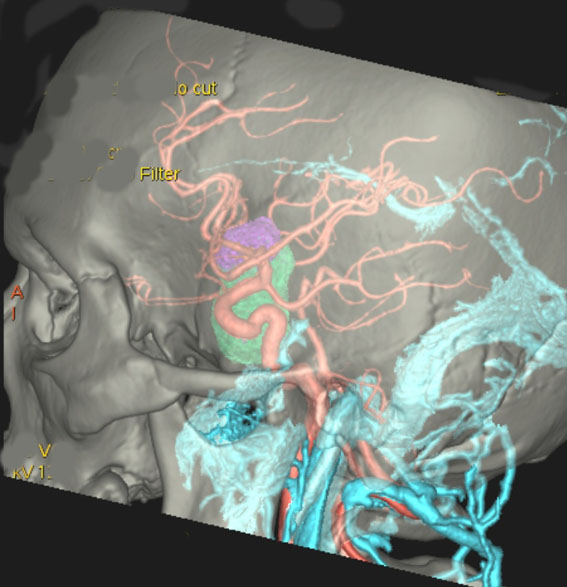

左は下垂体腺腫(緑の腫瘍)が内頚動脈に挟まれていることを示しています。

中央は手術前の下垂体腺腫で,視神経も正常下垂体も位置はわかりません。

右は手術翌日の画像です。黄色の矢印の先が残した正常下垂体組織です。桃色の矢印の先に視神経(視交叉)がはっきり見えています。術後の一時的な尿崩症がありました。クモ膜が残っているので髄液漏は生じませんでした。でも正常下垂体組織(黄色矢印)も視交叉も腫瘍に圧迫されてペラペラになっていますから,いつもうまく行くとは限りません。